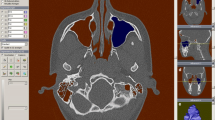

The midsagittal plane was also used for mirroring the healthy or less affected side to the contralateral side in order to represent the severity of asymmetry of the bone segments. Figures 1, 2, and 3 show surface rendering technique and multiplanar reconstructions in the three orthogonal planes of a patient: all these images are easily obtained and available for surgery planning.

CT-based reconstructions of patient #04 obtained to better show the bone structure asymmetry. The left column report the native images while in the right column the left hemiskull is mirrored on the right side. a, b Surface rendering technique, frontal view. c–h Multiplanar reconstruction images on axial (c, d), coronal (e, f), and sagittal (g, h) planes. In this patient, both maxilla and mandible are particularly affected